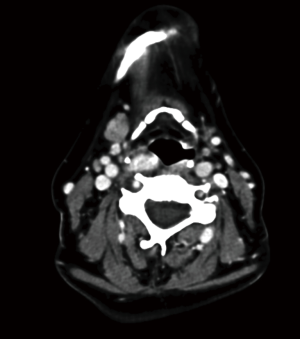

Case 1 underwent a bilateral neck exploration (BNE) for a thyroid nodule and primary HPT. A right thyroid lobectomy and left inferior parathyroidectomy were performed, with the pathological findings of benign thyroid nodule and parathyroid adenoma. Three normal parathyroid glands were identified. Hypercalcemia persisted and a both scintigraphy and a CT scan revealed a second undescended adenoma sitting on a fifth gland (Figure 1) that was confirmed at reoperation. Intraoperative PTH showed a curative descent from 239 to 69 pg/mL. The patient has remained normocalcemic for five years.